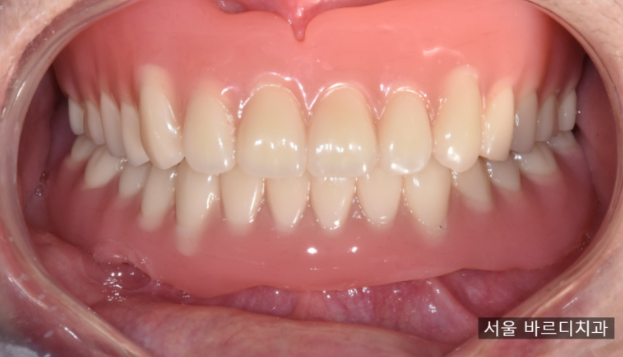

240103

완성한 사진입니다.

겉으로 보기에는 틀니이죠~?

x-ray로 확인해 보면 임플란트가 잘 심어진 것을

확인하실 수 있습니다.